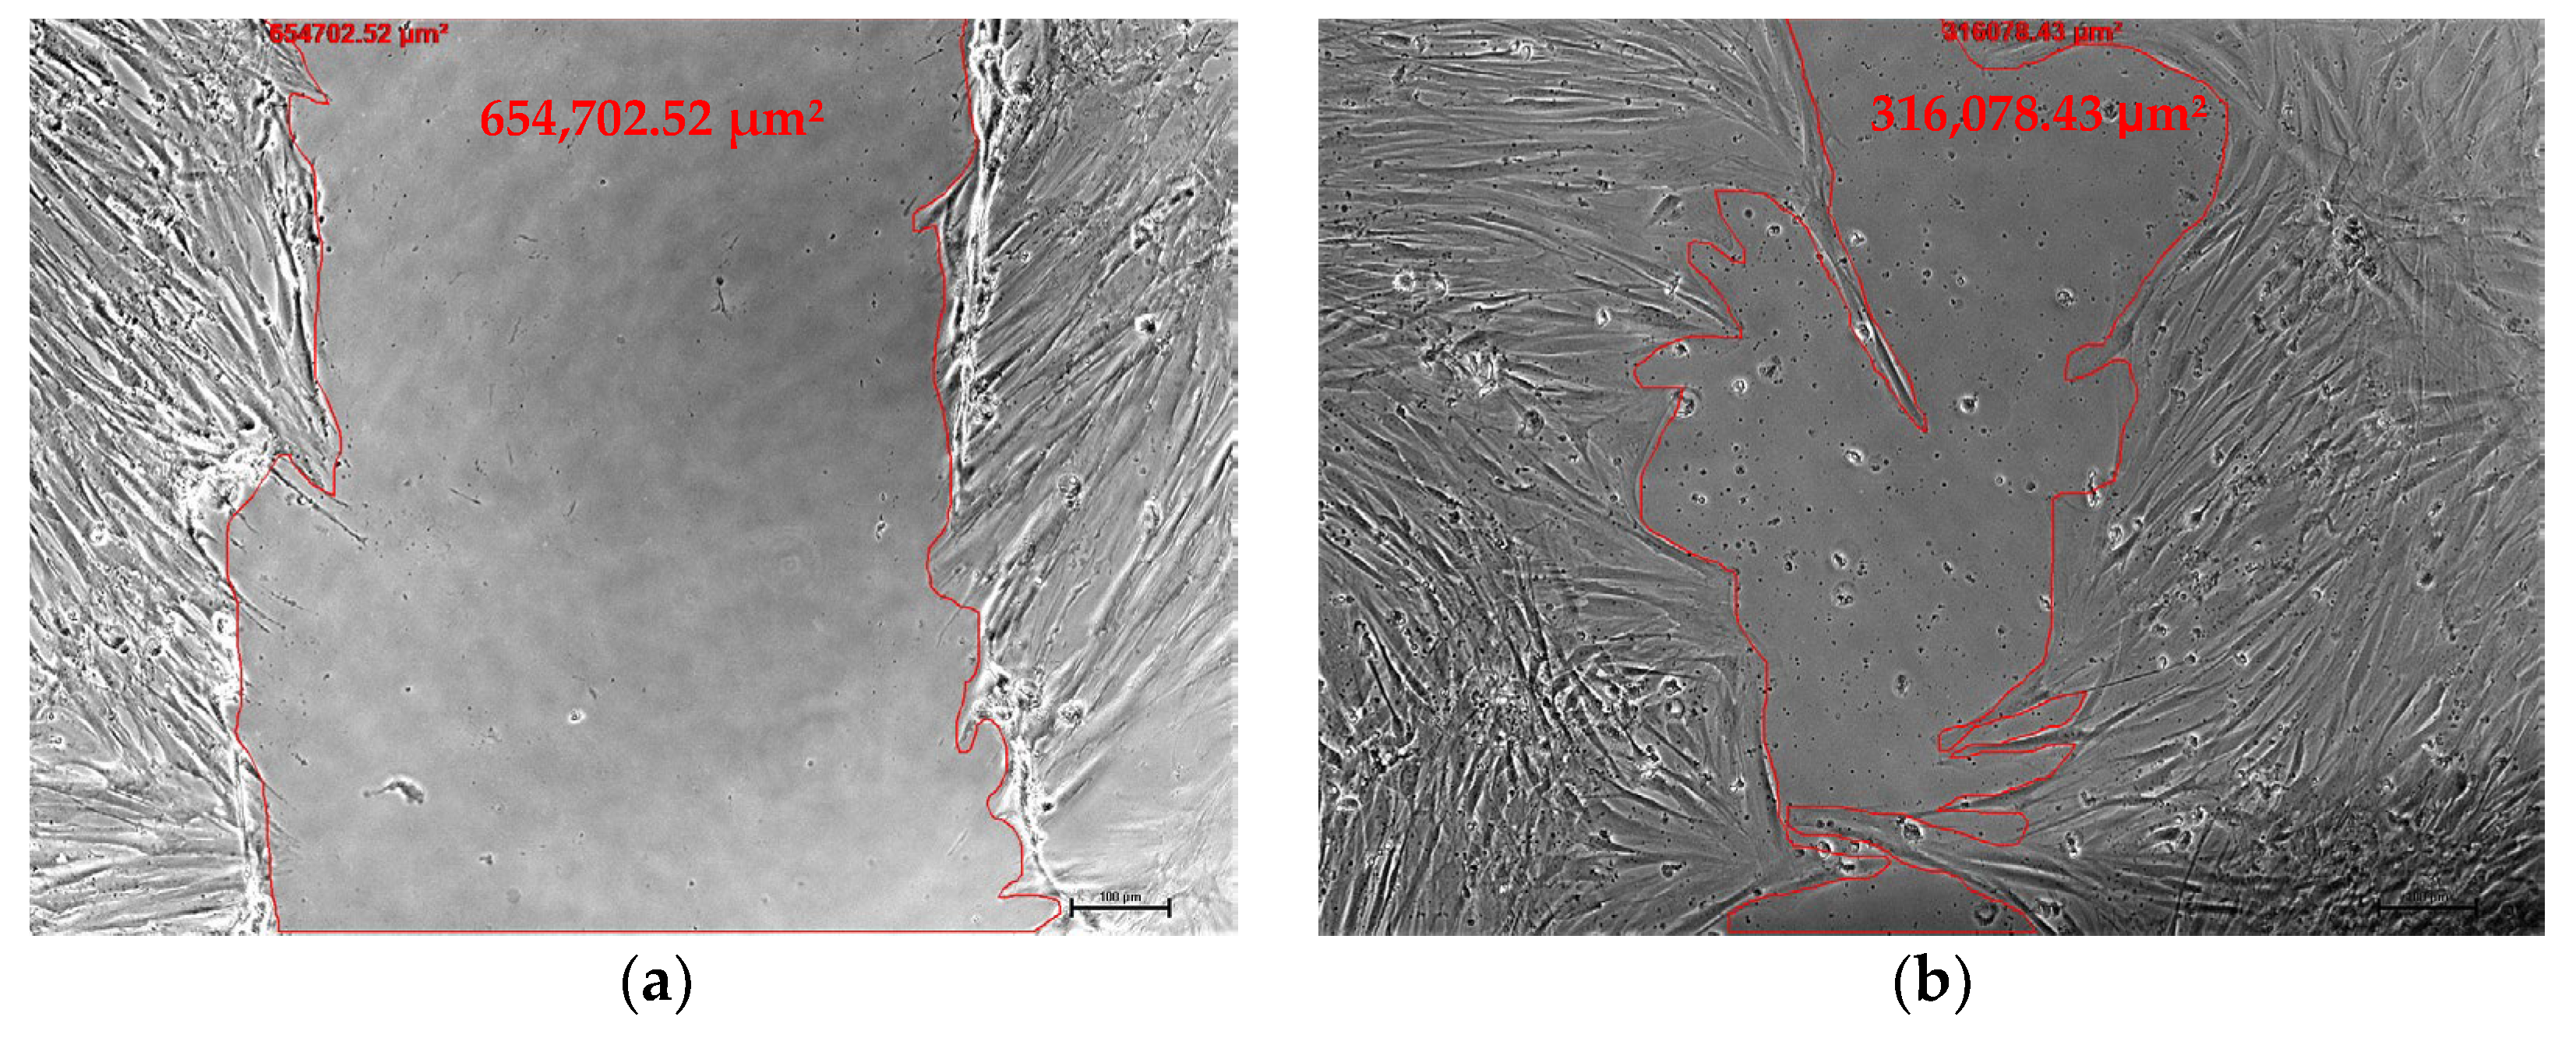

2.2. Cell Migration in Wound Healing

4.3. Wound Scratch Assay